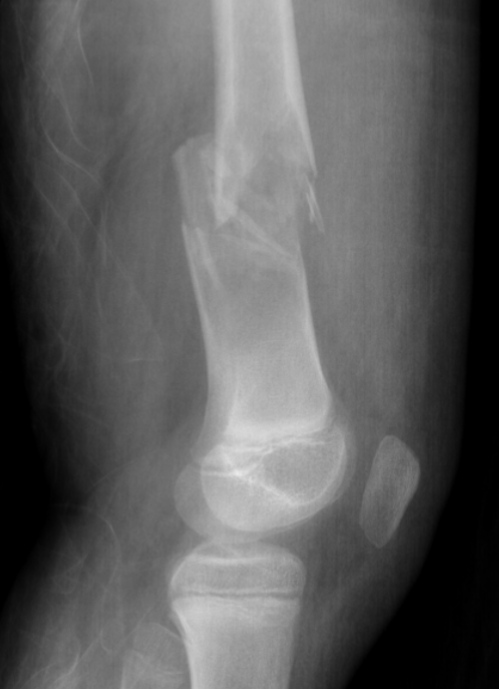

X-ray

Well-defined lucency

- thin sclerotic rim

- usually central

- thinned cortex with slight expansion

- thin internal septa

- can be multi-loculated

Fallen-Leaf (AKA fallen-fragment)

- with pathological fracture

- indicates that the lesion has no matrix and is fluid filled

Fallen leaf sign

DDx ABC